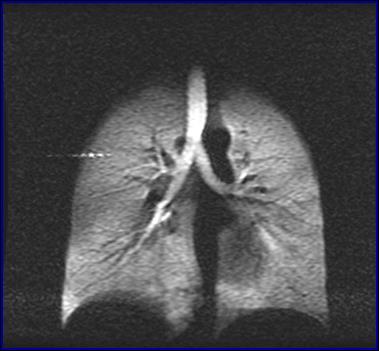

星天地娱乐城官网 武汉物理与数学研究所研究员周欣、中科院院士叶朝辉带领的科研团队克服技术难关,研制出具有自主知识产权的人体肺部气体磁共振成像系统。该系统弥补了传统磁共振成像不能检测肺部空腔结构的缺陷,成功“点亮”人体肺部,且能同时获得肺部气气、气血交换的功能信息,成为肺癌等重大疾病早期科学研究和诊断的新利器。目前,该成果已转移转化成立产业化公司,且正在申请医疗器械注册证。2018年7月在同济医院建立了第一个肺部气体磁共振临床检测中心,用于大规模临床病例获取工作。

左:核心装置超极化气体发生器 右:我国首幅人体肺部气体磁共振成像图